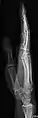

AP and lateral elbow X-ray

Extremities

A projectional radiograph of an extremity confers an effective dose of approximately 0.001 mSv, comparable to a background radiation equivalent time of 3 hours.[16]

The standard projection protocols in the UK are:[15]

• Elbow - AP and Lateral. Radial head projections available on request

• Radius and Ulna - AP and Lateral